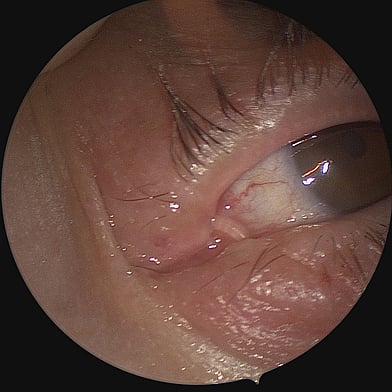

The endoscope is inserted through the nasal cavity to visualise and access the lacrimal sac and nasal bones. The bone is drilled away endoscopically, and a similar new pathway is created without external incisions. A mucosal flap is created to line the new passage connecting the lacrimal sac to the nasal cavity, ensuring proper drainage of tears. Silicone tubes or stents may be placed temporarily to keep the new pathway open and aid in healing.